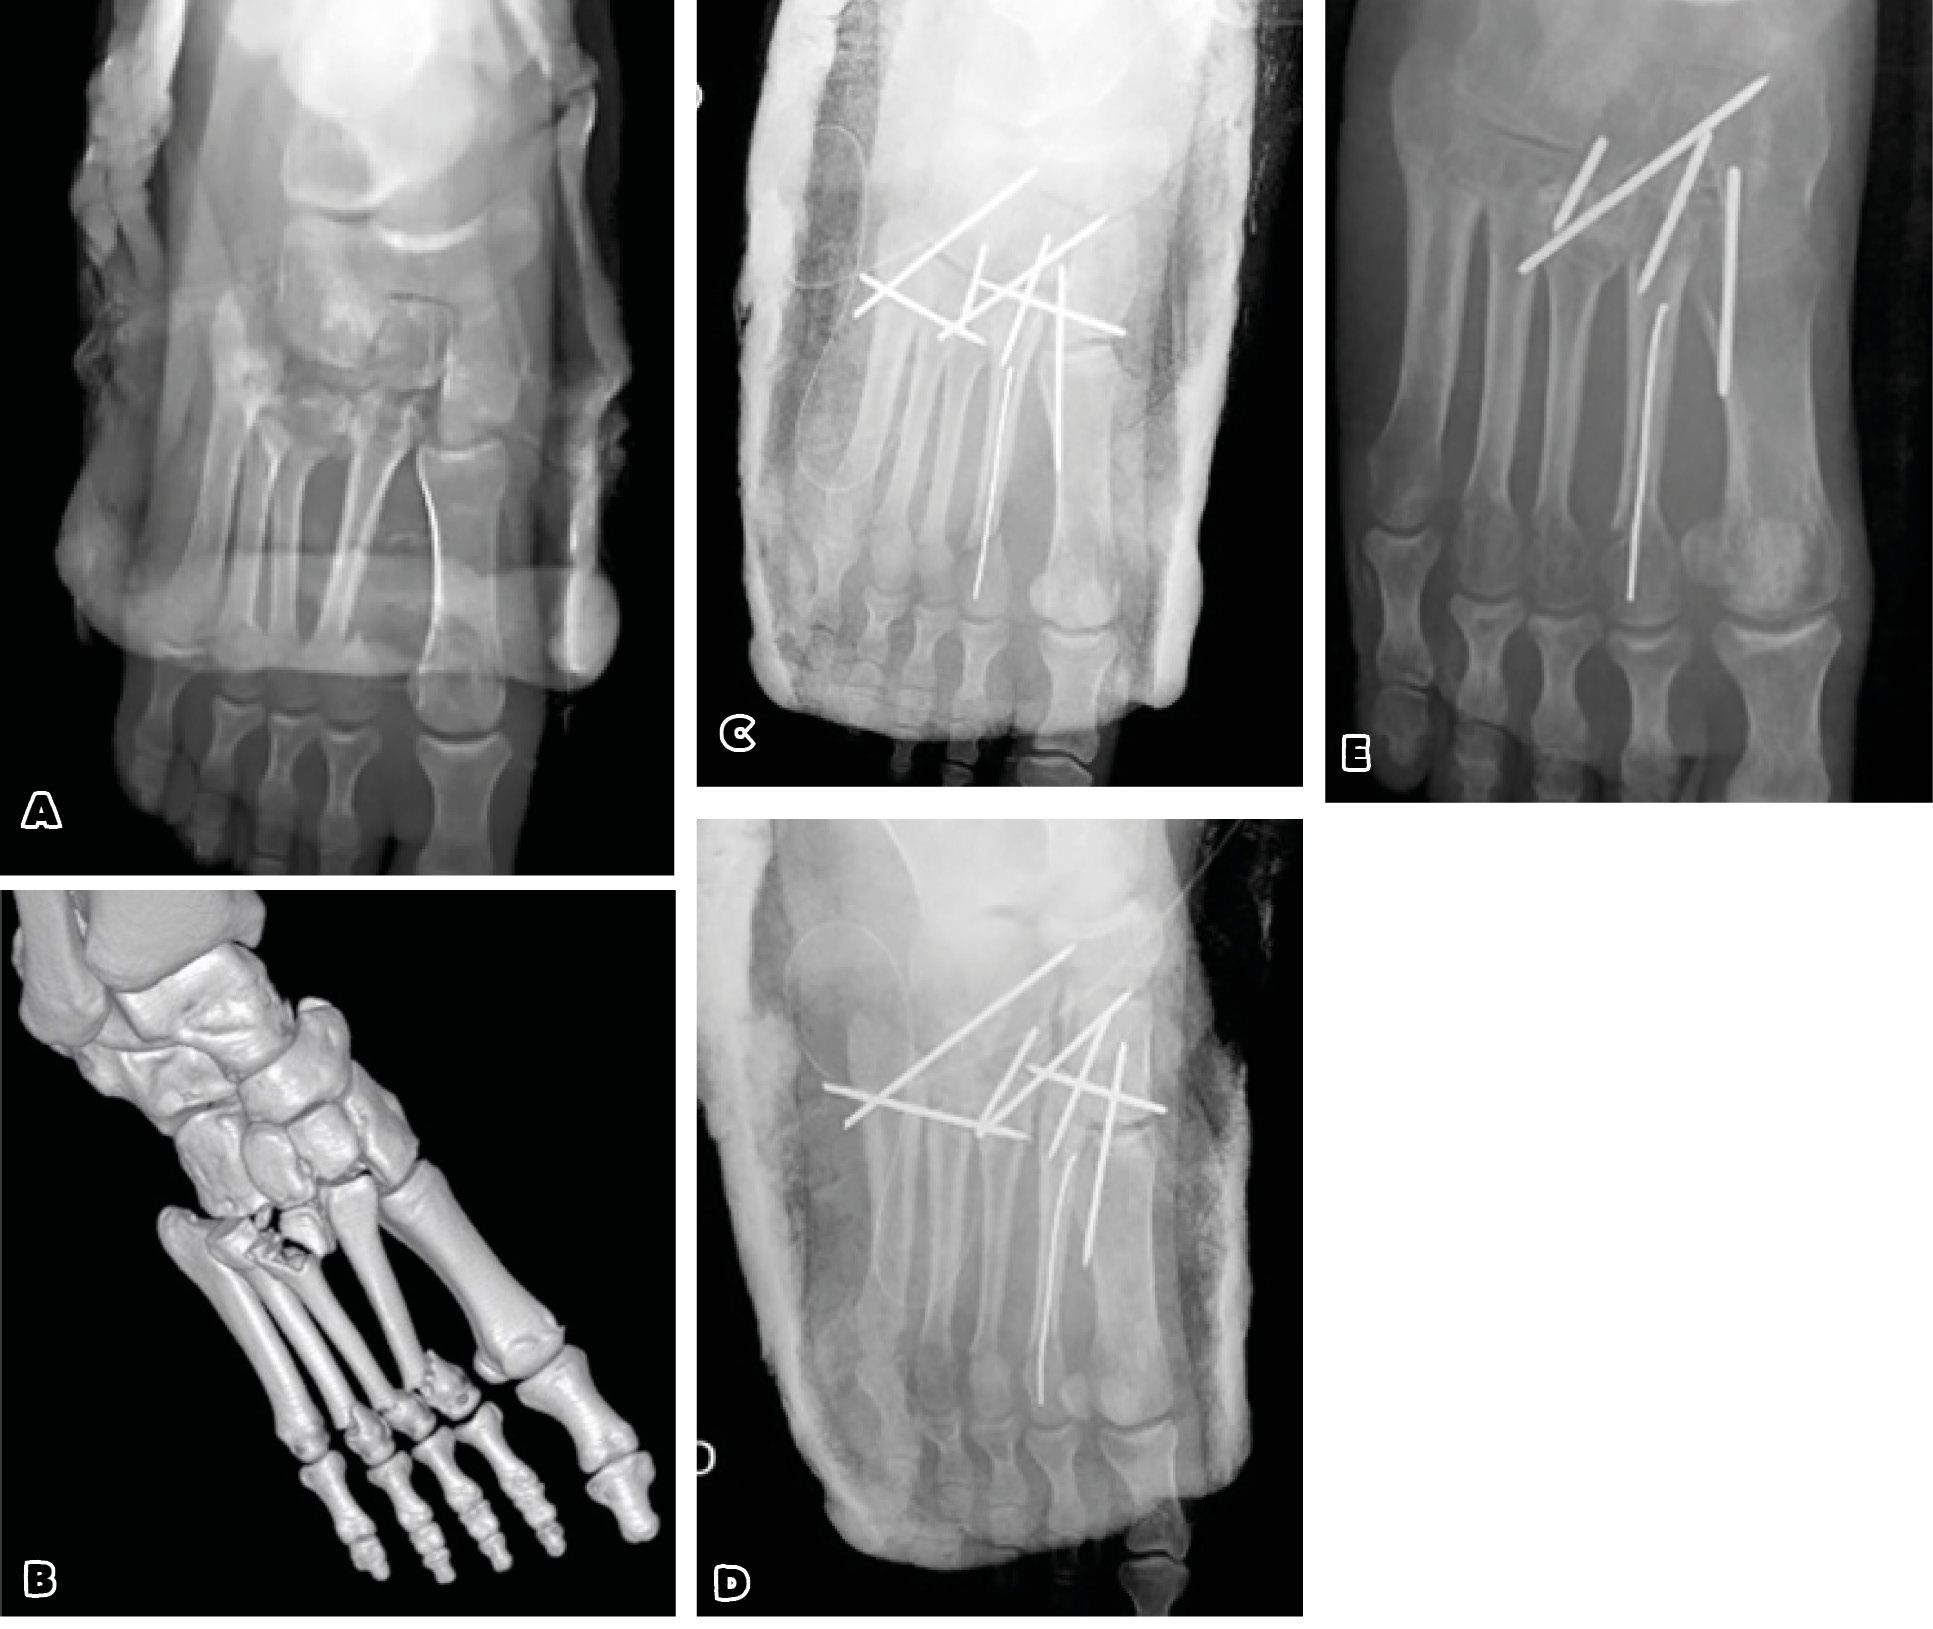

However, the reduction must be anatomical, otherwise an open reduction will be necessary. Bloody reduction is preferred by some authors. It may be postponed in case of skin pain or risk of postoperative skin complications. One or more sufficiently spaced longitudinal dorsal incisions are usually used depending on the location of the anatomical lesions, respecting the underlying vascular and nerve structures. Fixation can be provided either by Kirchner wires or by screwing. The fixation sequence will be from medial to lateral. It is important to reduce the base of the 2nd metatarsal in its mortise. When the fixation of the medial Lisfranc is accompanied by a satisfactory reduction of the lateral metatarsals, it is not useful to fix them systematically, which allows a certain lateral mobility to facilitate the adaptation of the step to the ground. (Case 1)

Case 1: 25-year-old woman. Road accident

Initial X-rays: fractures of necks M2-3-4 and damage 2nd-5th TMT joint

Percutaneous osteosynthesis reduction by multiple pinning and FU 1 year